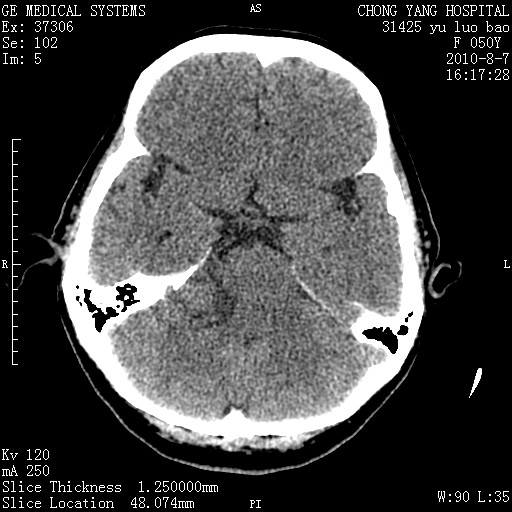

右侧桥小脑角区占位--听神经瘤,建议增强或mri检查。

右侧桥小脑角去等密度占位,右侧内听道扩大、骨质吸收,考虑:右侧听神经瘤,建议增强检查。

考虑听神经瘤可能性大。

右侧内听道扩大、骨质吸收,中脑受压左移,考虑:右侧听神经瘤,建议增强检查。支持!

右侧桥小脑角区等密度占位,内耳道扩大,听神经瘤